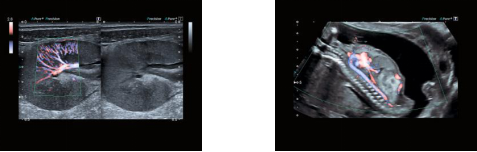

u 全新一代高级动态血流成像技术ADF(Advanced Dynamic FlowTM)

该技术是东芝公司独创的彩色多普勒成像技术,具有高分辨率、高敏感、高帧频的血流成像特点,可以高分辨显示微细血流信息,其优异的成像得到了广大专家的喜爱和充分认可。

铂金Aplio400采用全新一代高级动态血流成像技术,基于HD-B成像引擎,利用多普勒成像的宽带发射和接收技术(传统的彩色多普勒成像采用窄带发射和接收),突破性地从原理上提高了血流成像的分辨率,与此同时,血流的敏感度进一步提高、成像帧频进一步提升。

高级动态血流技术具有极大的应用价值,在众多应用领域都有其临床优势,如肿瘤等占位性病变微细滋养血管的显示;乳腺、肝肾、胰腺等各种器官的细微血管的显示;断肢再植血管的显示;胎儿心血管系统的显示等等,该技术可以广泛应用于各种肿瘤的良恶性鉴别、多器官的血流动力学研究、胎儿先天性心血管疾病的诊断等众多领域。